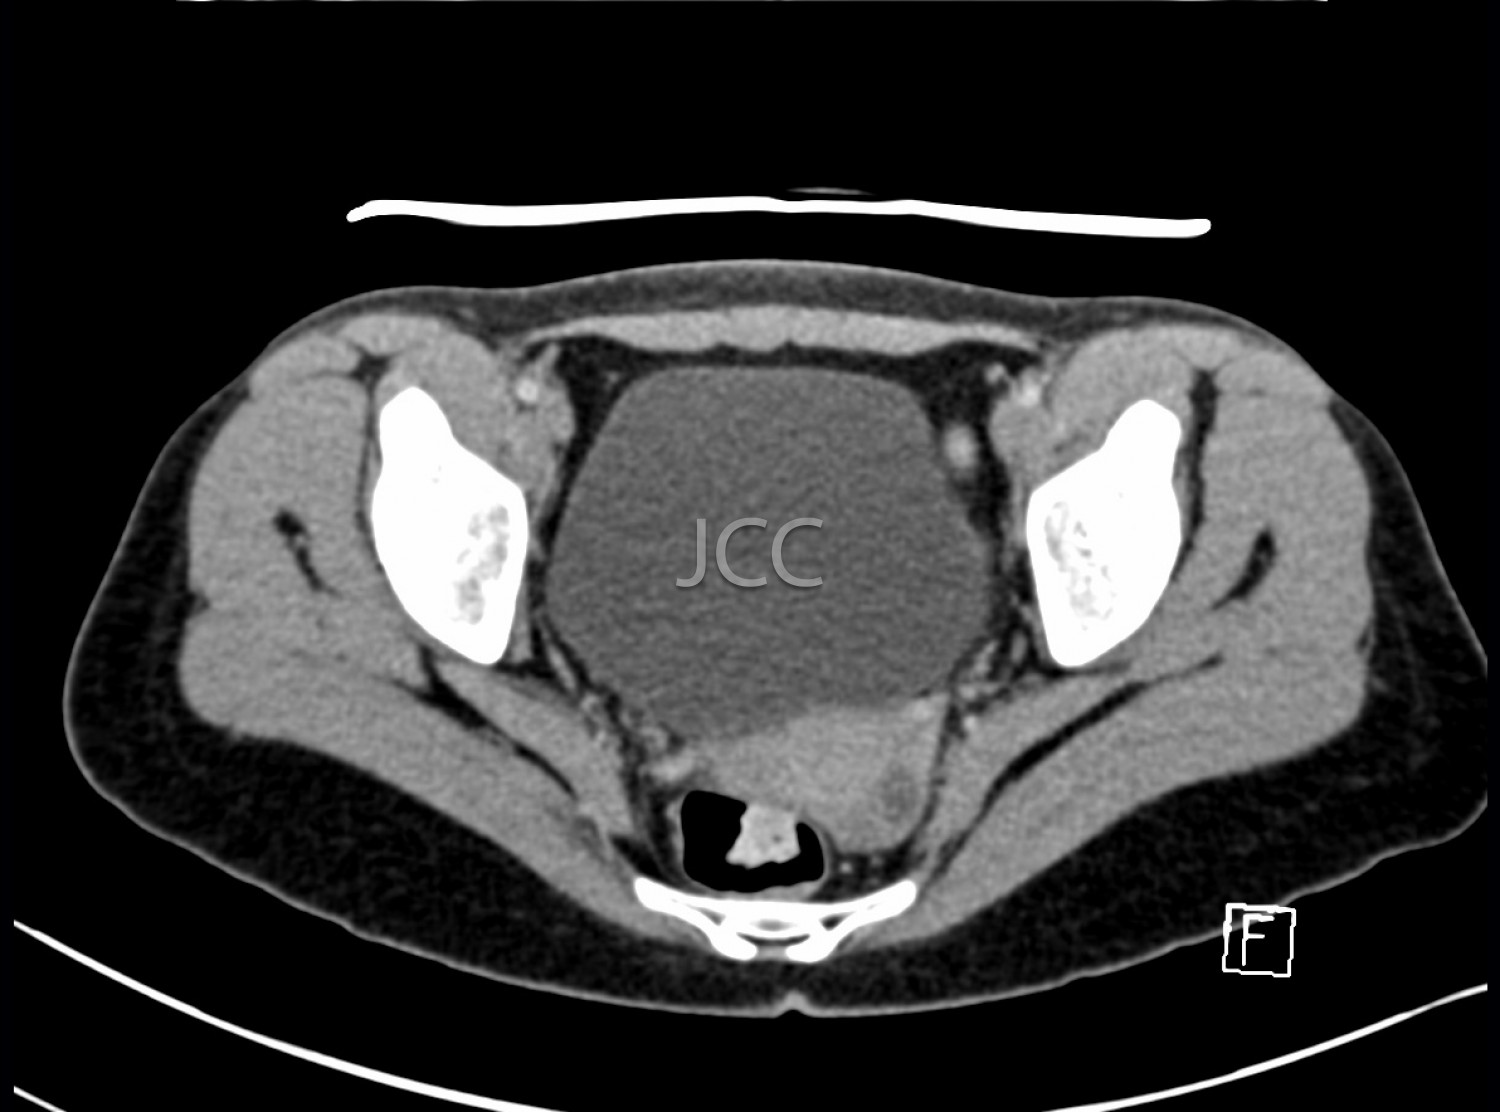

Computed Axial Tomography - Pelvis CAT scan

Computed Axial Tomography (CAT) - Dual Energy- 256 slices is a diagnostic technique that allows the evaluation of various parts of the human body, including the lungs, liver, pancreas, kidneys, heart, vascular structures and bone structures.